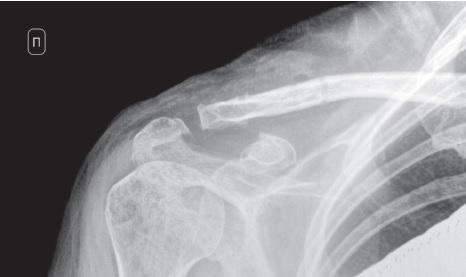

На рентгенограммах, выполненных на момент удаления имплантатов, также отмечаются признаки консолидации отломков и отсутствия подвывиха (рис. 4).

Рис. 4. Рентгенограмма правого акромиально-ключичного сустава в переднезадней проекции спустя 3 мес. после операции: признаки консолидации отломков и отсутствия подвывиха

Fig. 4. X-ray of the right AC joint in AP view 3 months after surgery. Signs of bone union without subluxation

В декабре 2022 г. в плановом порядке выполнено удаление крючковидной пластины с винтами из акромиального конца правой ключицы. Достигнуто клиническое выздоровление (рис. 5).

Рис. 5. Рентгенограмма правого акромиально-ключичного сустава в переднезадней проекции после удаления фиксаторов

Fig. 5. X-ray of the right AC joint in AP view after implants removal